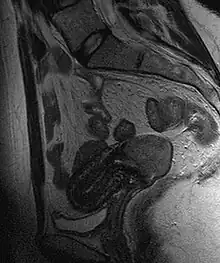

Often before the biopsy, the doctor asks for medical imaging to rule out other causes of woman's symptoms. Imaging modalities such as ultrasound, CT scan, and MRI have been used to look for alternating disease, spread of the tumor, and effect on adjacent structures. Typically, they appear as heterogeneous mass on the cervix.[47]

Location of cervical cancer and an example of normal and abnormal cells -

This large squamous carcinoma (bottom of picture) has obliterated the cervix and invaded the lower uterine segment. The uterus also has a round leiomyoma up higher. -